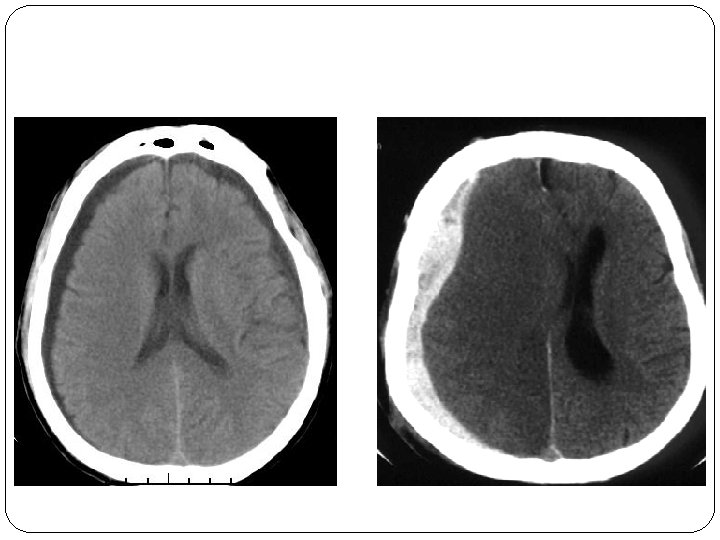

3 - PHYSIOPATHOLOGIE Les lésions peuvent être classées en lésions primaires et secondaires : Ø LES LÉSIONS PRIMAIRES inhérentes au traumatisme lui-même comprennent : * Les fractures du crâne * Les hématomes extra cérébraux, HSA * Les lésions intra parenchymateuses (contusions, lésions axonales diffuses). Ø LES LÉSIONS SECONDAIRES souvent plus dévastatrices que les atteintes primaires : * Engagements cérébraux et leurs complications vasculaires. * Œdème cérébral.

5 - INDICATIONS NEUROCHIRURGICALES À LA PHASE PRÉCOCE Il existe un consensus pour les indications de la chirurgie extra-parenchymateuse. Ces indications sont : – l’évacuation la plus précoce possible d’un hématome extradural symptomatique quelle que soit sa localisation. – l’évacuation d’un hématome sous-dural aigu significatif (épaisseur supérieure à 5 mm avec déplacement de la ligne médiane supérieur à 5 mm); – le drainage d’une hydrocéphalie aiguë; – le parage et la fermeture immédiate des embarrures ouvertes; – la réduction d’une embarrure fermée compressive

INDICATIONS NEUROCHIRURGICALES À LA PHASE PRÉCOCE Par contre, la gestion des lésions parenchymateuses (hématome, contusion) est souvent discutée, au cas par cas, en fonction de leur localisation, de leur taille et de leur implication dans l’hypertension intracrânienne. La plupart des équipes adoptent une attitude conservatrice sauf dans trois situations bien définies : – un hématome intracérébral ou une contusion hémorragique, d’un volume supérieur à 15 ml, avec déplacement de la ligne médiane supérieur à 5 mm et oblitération des citernes de la base, doit être évacué le plus précocement possible; – l’existence d’une anisocorie associée à une contusion temporale est une indication à faire une lobectomie temporale polaire; – devant la présence d’une contusion frontale unilatérale associée à une HIC non contrôlée malgré un traitement antiœdémateux adéquat il est nécessaire de discuter une lobectomie frontale. La craniotomie décompressive sera envisagée plus loin, dans le